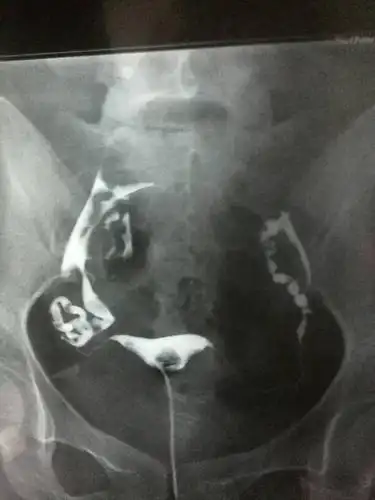

输卵管积水用哪些方法可以诊断原创

如何看懂输卵管堵塞,粘连,积水造影片子!

问:昨天做了输卵管造影,检查诊断是,右侧输卵管积水,两侧输卵管上举

这是输卵管造影 输卵管积水 做完后医生直接跟我说把输卵管结扎做试管